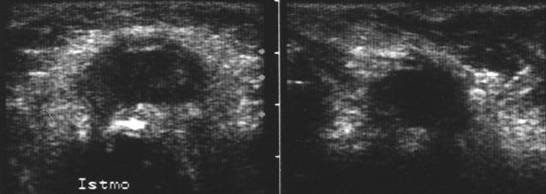

Lob drept , proiectie trasversala si longitudinala.

Femeie 19 ani. Leziune marcant hipoecogen cu intarire posterioara, de 16x20x26mm (4 cc) in lobul drept.

Examen citologic: macrofagi, fara tireocite.